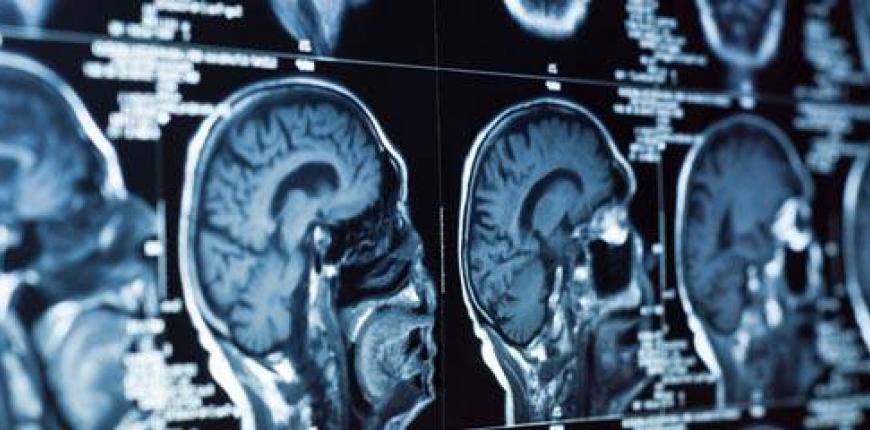

Boğaziçi Üniversitesi Biyomedikal Enstitüsü’nde doktora çalışmalarını sürdüren Abdullah Baş, ekipçe biyomedikal alanında çalıştıklarını belirterek, “Hepimiz biyomedikal mühendisiyiz. Beş kişinin üçü halihazırda yapay zekâyla ilgileniyor. Bu yarışmanın başvuruları açıklandığında, rapor istenen aşamayı geçtikten sonra yarışma özelinde çalışmaya başladık. Üniversitede de benzer olarak medikal görüntüleme üzerine çalışıyoruz. Ben beyin MR’ı konusunda araştırmalarımı sürdürüyorum” diyor.

“Sağlıkta Yapay Zekâ Yarışması için bilgisayar tomografi (BT) görüntülerinde beyin dokusunda inme, kanama ve iskemiyi segmente edecek bir yazılım oluşturmamız bekleniyordu. İlk önce sadece inme olup olmadığının sınıflandırmasının beklendiği bir ön eleme aşaması vardı. O aşamayı geçenlerle de segmentasyon aşamasına geçiliyordu. İnme, iskemi ve kanamayı sınıflandıracak bir model bekleniyordu. Biz açıkçası finale kalmayı bekliyorduk, o açıdan biraz hayal kırıklığımız oldu. Biz daha optimizasyonları yapmamışken yüzde 90’lık bir başarı sağlamıştık sınıflandırmada. Birinci olanlar yüzde 96 başarı sağlamış. Optimizasyonları yaptıktan sonra çok rahatlıkla benzer bir başarı yakalayabilirdik.”